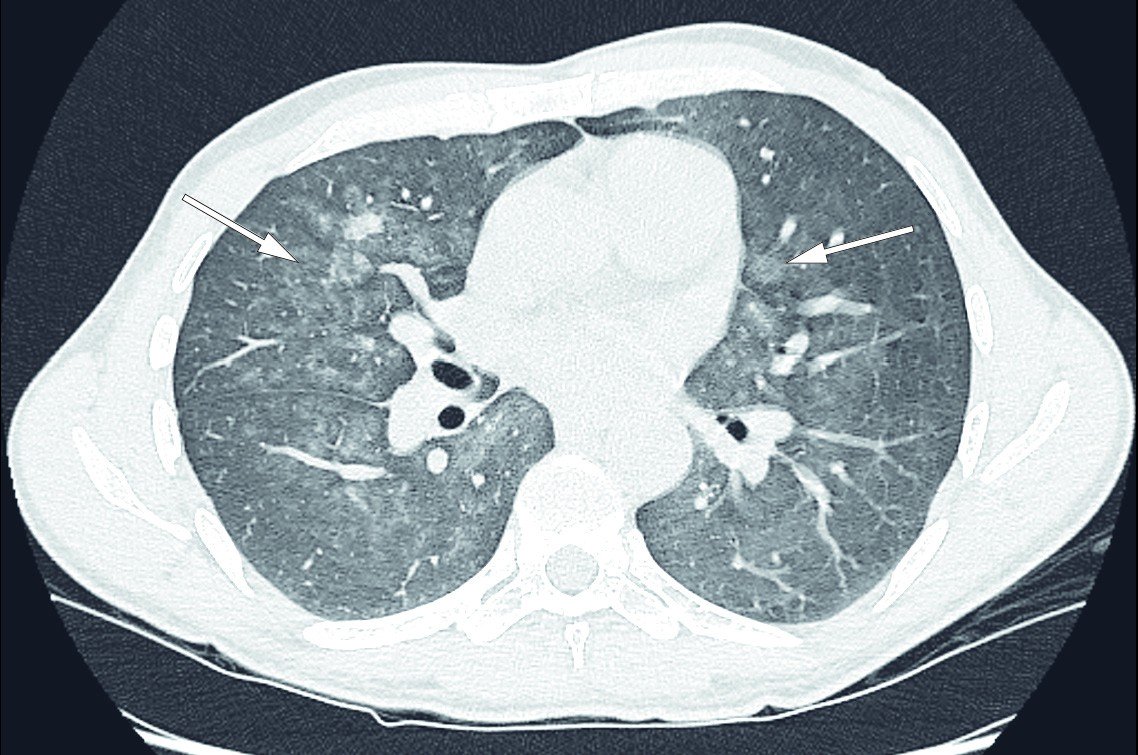

Sykdommen covid-19 (coronavirus disease 2019), forårsaket av sars-CoV-2 (severe acute respiratory syndrome coronavirus 2), sprer seg nå som en pandemi. De fleste vil ikke bli alvorlig syke, men blant de som trenger intensivbehandling på sykehus, er mortaliteten høy. Massiv lungeaffeksjon og akutt lungesviktsyndrom (ARDS) preger disse pasientene. I mange tilfeller vil en også kunne se kraftig systemisk og lokal inflammasjon som kan bidra til å forverre tilstanden. Bakgrunnen for fenomenet er ikke kartlagt, men det er vist at sars-CoV-2 kan aktivere inflammasomer i det medfødte immunforsvaret, med frigjøring av interleukin-1, gjennom binding til angiotensinkonverterende enzym 2 i lungevevet (6). Ved covid-19 ser man også en massiv frigjøring av interleukin-6. Det er ikke utenkelig at en slik «cytokinstorm» kan føre til utvikling av sekundær hemofagocytisk lymfohistiocytose med cytopenier, betydelig hemofagocytose i beinmarg og lav fibrinogenkonsentrasjon. Høye ferritinnivåer og persisterende høy CRP kan vekke mistanke om at en cytokinstorm er en del av sykdomsbildet.